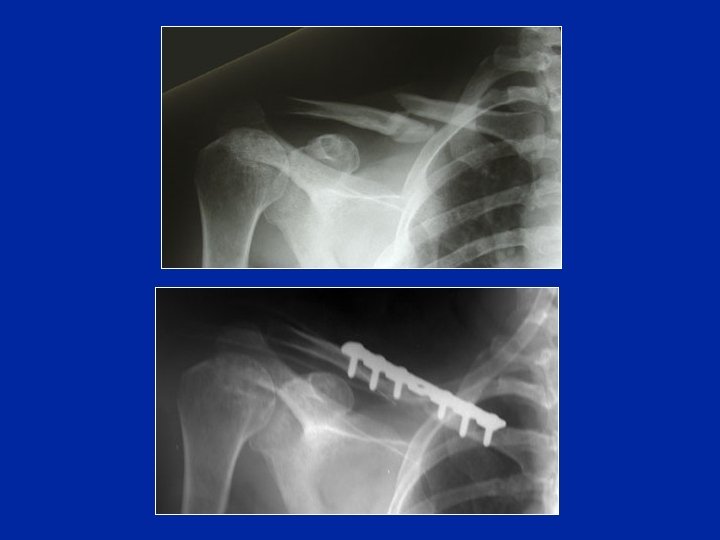

Traitement chirurgical Broche Plaque supérieure Plaque inférieure

Traitement chirurgical Avantages Anatomie rétablie Mobilisation douce précoce Inconvénients Dépériostage Dévascularisation Retard de consolidation Infection possible

Traitement chirurgical Fractures distales : hauban (broches et fil en 8)